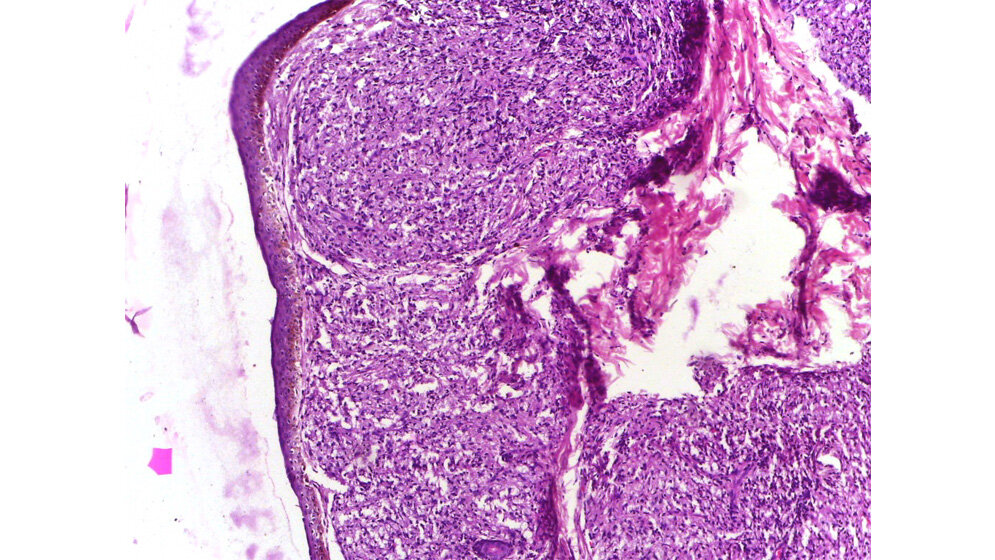

Es soll sich laut Angaben des RKI um eine Borderline Lepra handeln. Das heißt, es handelt sich um eine Mischform. Der Verlauf ist abhängig vom Immunstatus des Patienten. Je nach Resistenzlage kann es sich um eine eher der tuberkuloiden Lepra oder eine eher der lepromatösen Lepra entsprechenden Symptomatik handeln. Ob es sich schon um die lepromatöse Form der Lepra handelt, war noch nicht in Erfahrung zu bringen. Diese verläuft ähnlich wie die Miliartuberkulose progressiv mit zahlreichen Läsionen und vielen Bakterien. Sie ist hoch infektiös und deshalb besonders gefährlich. Laut Informationen der TK nimmt sie oft einen wesentlich dramatischeren Verlauf. Wenn der Körper nicht in der Lage ist, die Bakterien zu bekämpfen, können sie sich nahezu ungehemmt vermehren und Schwellungen und schwerste Gewebeschäden verursachen. Am ganzen Körper können Hautpapeln (Knötchen) und Knoten auftreten. Meist ist das Gesicht mit Nase und Ohren, später auch Hände, Arme und die Gesäßregion betroffen. Augenbrauen und Wimpern fallen aus.

Bei dem Erkrankten handelt es sich um einen indischen Staatsangehörigen. Die Erkrankung wurde entdeckt, als er wegen Hautveränderung einen Dermatologen aufsuchte. Es handelt sich um Borderline-Lepra. Es wurden keine Kontaktpersonen in Deutschland angegeben, zu welchen der erforderliche enge Hautkontakt bestand.